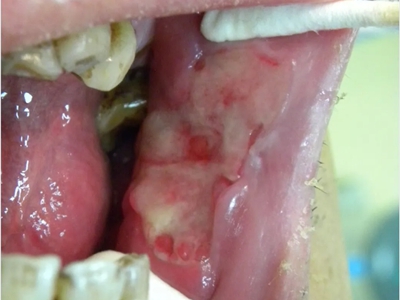

口腔

肉赘

颊癌口腔黏膜有突出性肉赘图

颊癌患者一侧颊黏膜上出现不规则的凸起性肉赘,上有颗粒状肉芽,附有少量黄白色脓液,肉赘周围口腔黏膜附有一层较厚的白膜,提示癌变处于进展的状态。